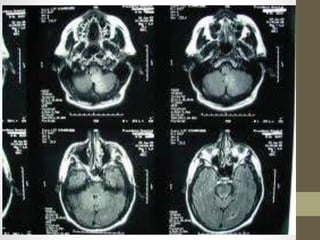

DIAGNOSTIC STUDIES

• Computed tomography angiography.

• Magnetic resonance angiography

• Single photon emission computed

tomography (SPECT)

• Positron emission tomography (PET)

• Magnetic resonance spectroscopy (MRS)

• Xenon CT

• Electroencephalogram

• Cerebral angiography

• Cerebrospinal fluid analysis